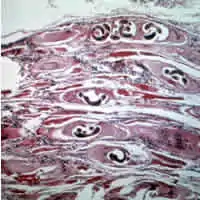

Trichinella larvae in pressed bear meat, partially digested with pepsin. The classic coil shape is visible. | |

- Animal tissue infected with the parasite that causes the disease trichinosis: Most parasites are shown in cross section, but some randomly appear in long section.